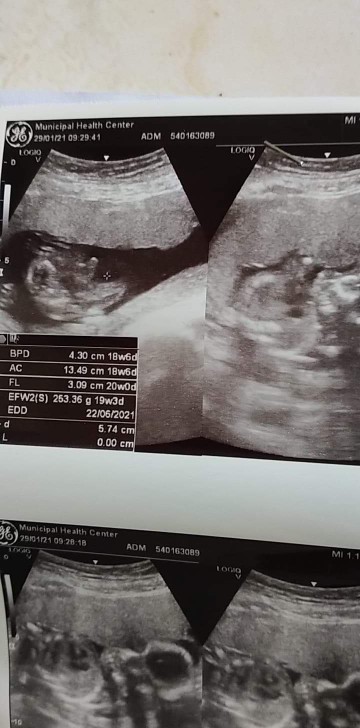

16+4 ยังไม่ทราบเพศเลยค่ะหมอไม่ได้บอกอะไรเลย